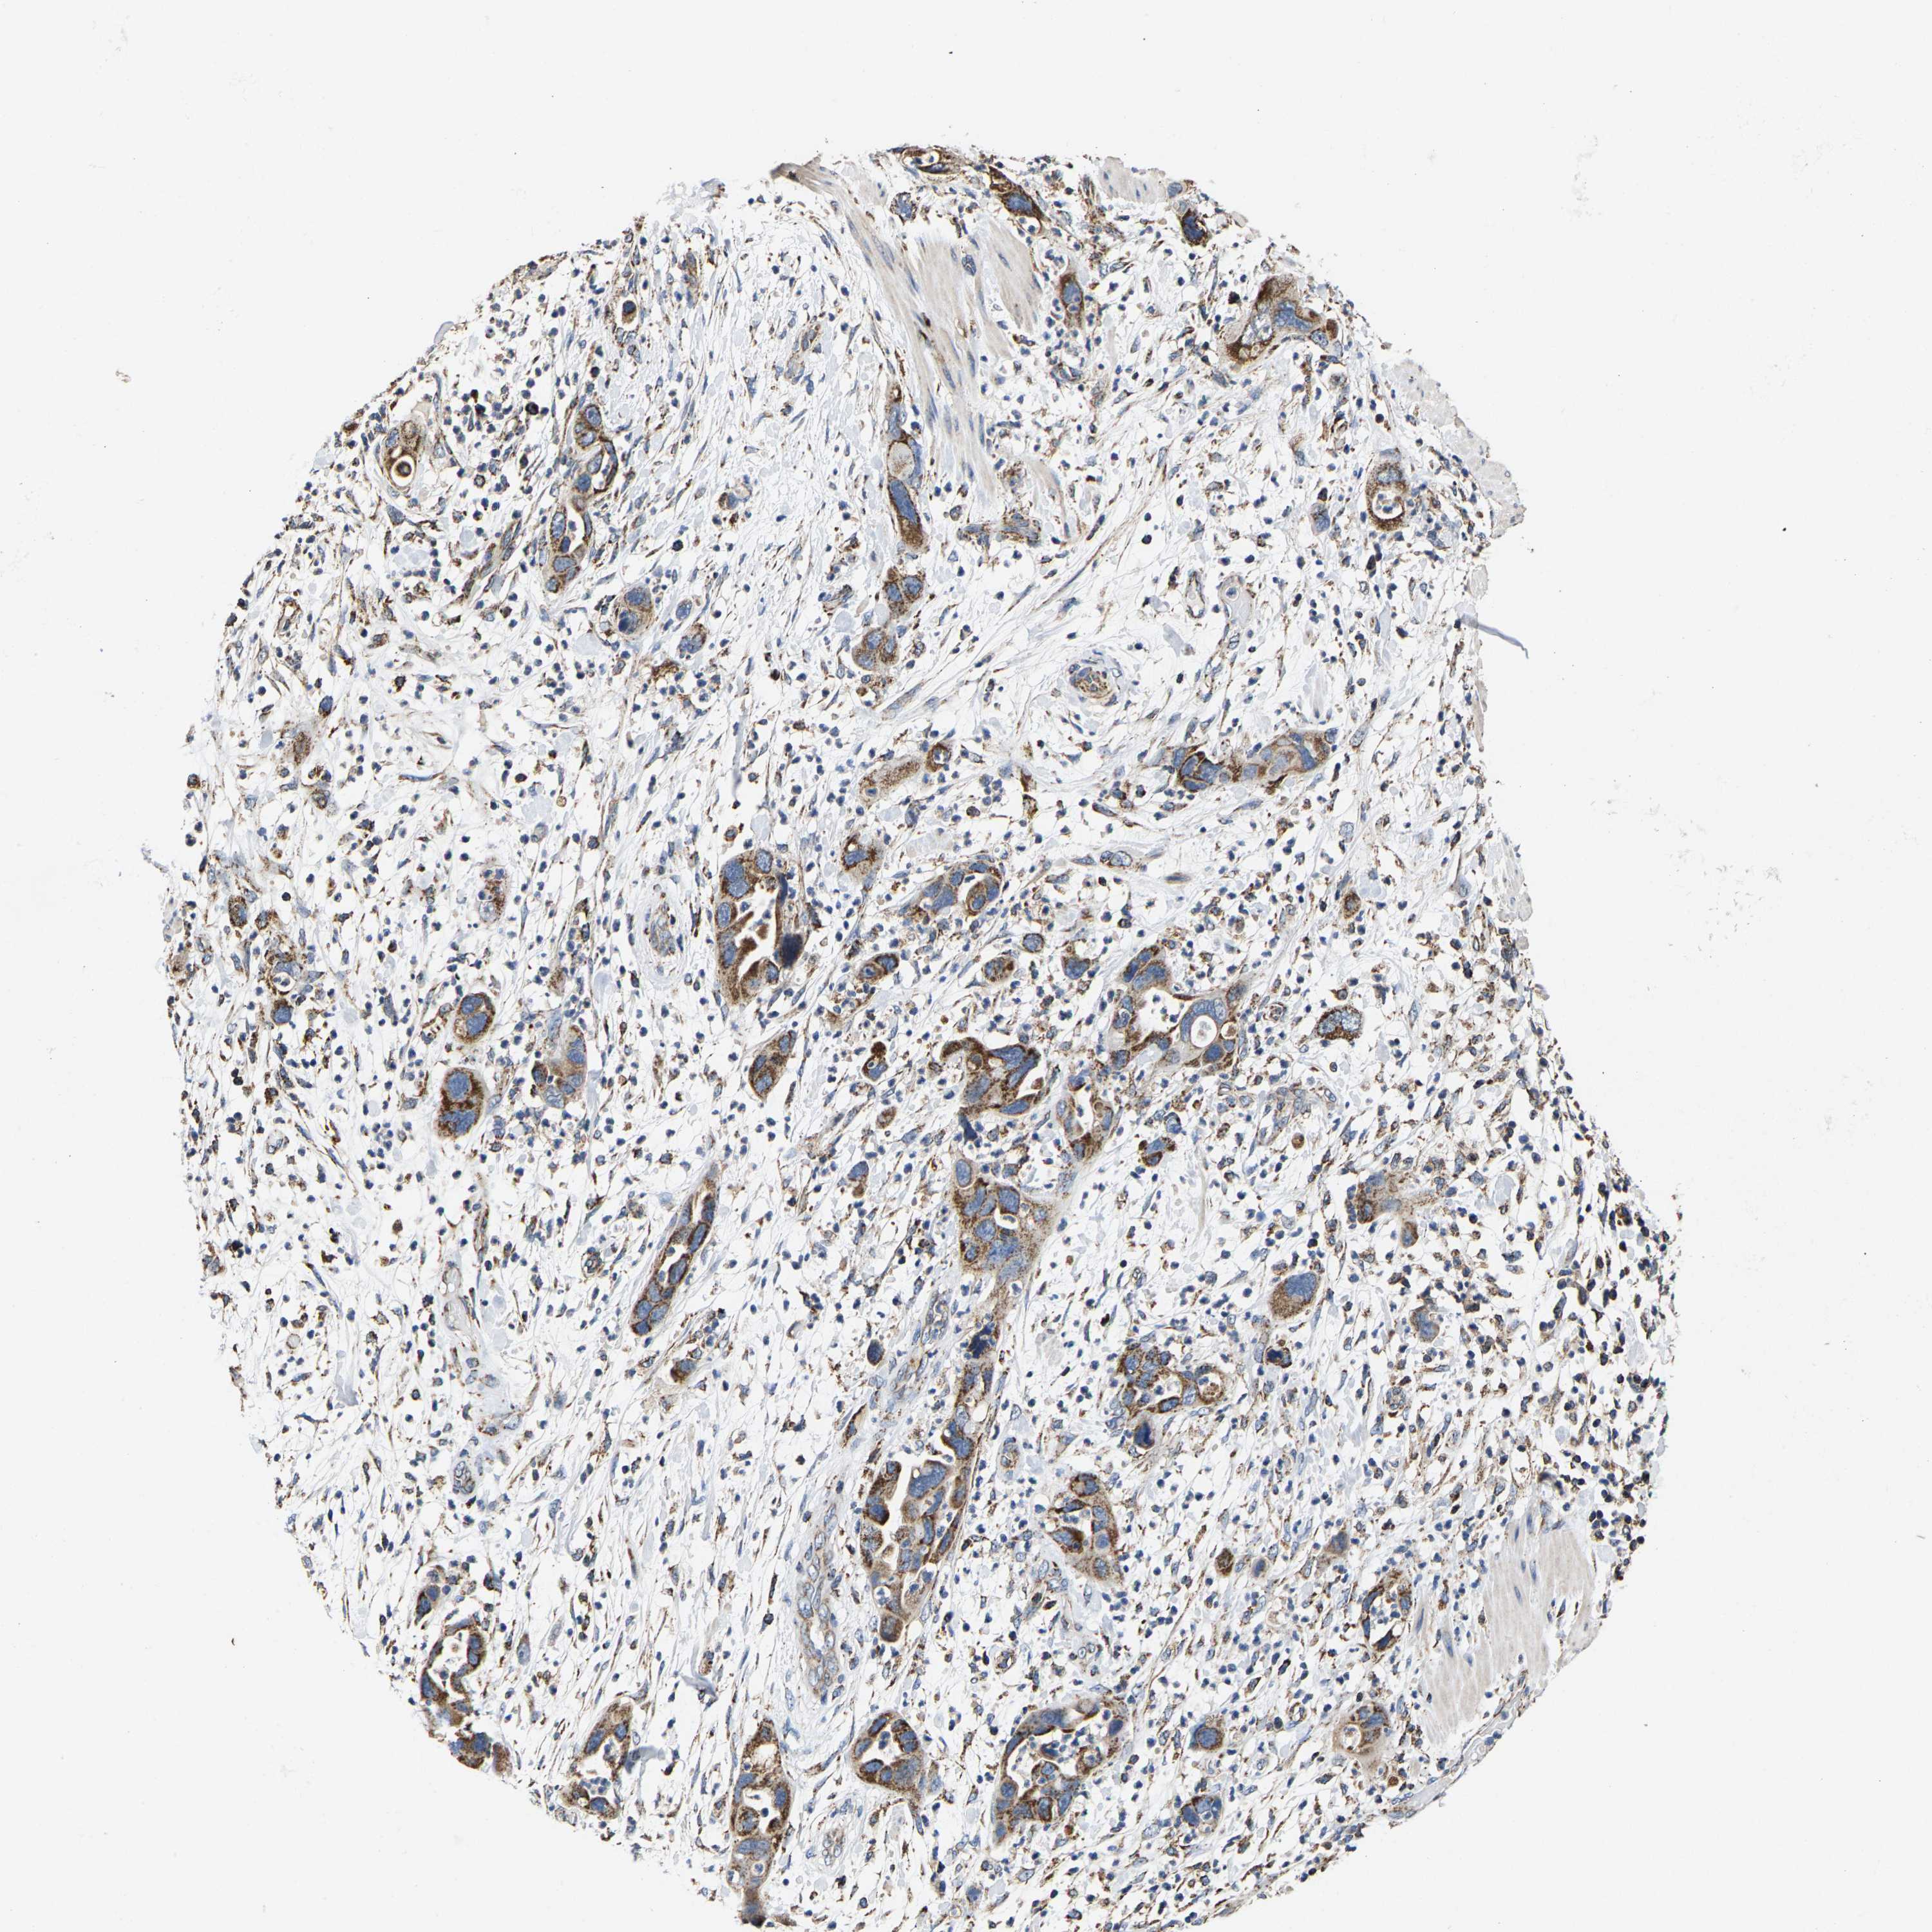

PANCREATIC CANCER - Protein expressioni

A mouse-over function shows sample information and annotation data. Click on an image to view it in a full screen mode. Samples can be filtered based on level of antibody staining by selecting one or several of the following categories: high, medium, low and not detected. The assay and annotation is described here.

Note that samples used for immunohistochemistry by the Human Protein Atlas do not correspond to samples in the TCGA dataset.

Antibody stainingi

Antibody staining in the annotated cell types in the current human tissue is reported as not detected, low, medium, or high, based on conventional immunohistochemistry profiling in selected tissues. This score is based on the combination of the staining intensity and fraction of stained cells.

Each image is clickable and will lead to virtual microscopy that enables deeper exploration of all samples and also displays staining intensity scores, fraction scores and subcellular localization as well as patient and tissue information for each sample.

Antibody HPA020543

Antibody HPA020549

Staining

High

Medium

Low

Not detected

Intensity

Strong

Moderate

Weak

Negative

Quantity

>75%

75%-25%

<25%

None

Location

Nuclear

Cytoplasmic/membranous

Cytoplasmic/membranous,nuclear

Adenocarcinoma, NOS